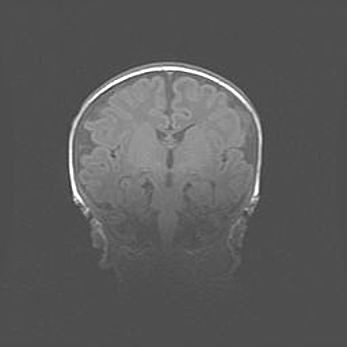

Множественные кисты обоих полушарий головного мозга, наибольшая из них в правой затылочной области. Ассиметричная атрофическая гидроцефалия.

Возраст: 7 месяцев

Вес: 5660 г

Пол: мужской

Окружность головы: 41,5 см

Срок гестации: 28-29 недель

Кисты головного мозга развиваются в результате многоочаговых некрозов вещества мозга и возникают вследствие перенесенной перинатальной инфекции, менингитов, энцефалитов, асфиксии, родовой травмы, расстройств мозгового кровообращения различного генеза. Образованию кист в веществе головного мозга плодов и новорожденных способствуют такие факторы, как высокое содержание в нем воды, недостаточная (или отсутствие) миелинизация и слабая астроглиальная реакция на повреждение.

Кисты могут сочетаться с гидроцефалией и другими поражениями головного мозга.